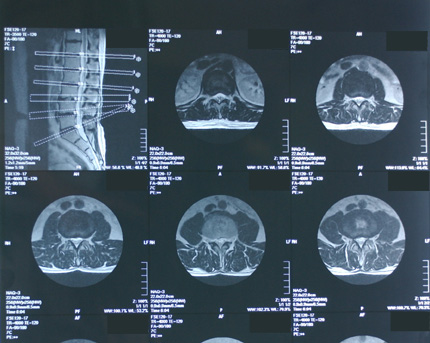

MRI画像からマップ画像を切り抜いて掲載し説明しましたが、MRIやCT画像を見慣れない方から

「マップ画像の意味が分からない」というメールを頂きましたので、画像を追加し説明します。

MRIやCT画像などでは、一枚の写真の中に複数の診断用断層画像とそれぞれの断層撮影画像の部位や断層角度を示す画像(写真右上)を添付します。 この部位角度を示す画像をマップ画像と呼びます。なお、本HPで掲載しているMRIやCT画像は、複数の診断用断層画像の一部を拡大したものです。

さらに、個人情報保護や解説用に画像処理を施していますので、本来のMRIやCT画像とは異なります。